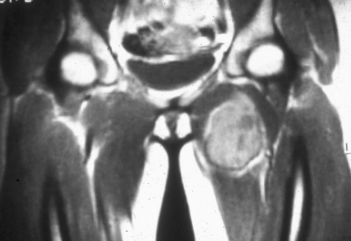

What is seen on MRI?